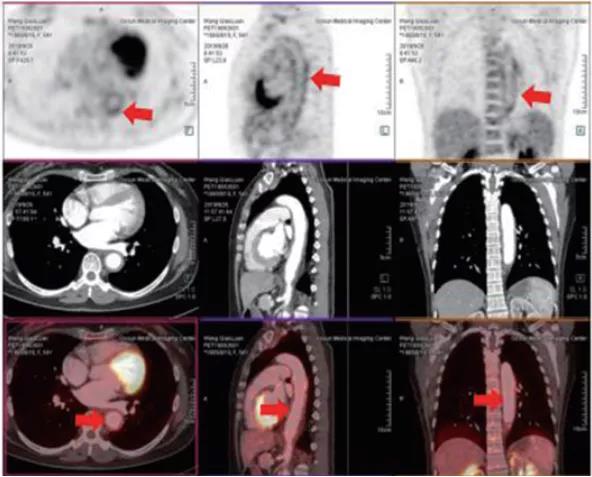

Biograph mCT Flow

臨床應(yīng)用:

一、腫瘤疾病的應(yīng)用

1、腫瘤的早期診斷和鑒別診斷

2、對(duì)惡性腫瘤進(jìn)行更準(zhǔn)確分期,全面了解全身病變情況

3、已發(fā)現(xiàn)腫瘤轉(zhuǎn)移者,尋找原發(fā)灶

4、腫瘤標(biāo)志物升高或副腫瘤綜合征患者,尋找腫瘤病灶所在

5、腫瘤治療后效果評(píng)估

6、腫瘤復(fù)發(fā)的監(jiān)測(cè)

二、非腫瘤顯像

1、癲癇患者癇灶定位2、風(fēng)濕免疫性疾病患者明確感染病變的部位、范圍及活動(dòng)程度,并評(píng)估療效3、早期診斷,并能準(zhǔn)確評(píng)估大血管炎的活動(dòng)情況三、PET/CT-MR的PET/MR融合技術(shù)應(yīng)用四、PET/CT-MR特色診斷技術(shù)

?精準(zhǔn):本設(shè)備是新一代PET/CT,圖像重建矩陣可達(dá)400×400,其分辨率達(dá)到毫米;其FlowMotion掃描技術(shù)提供極精細(xì)器官細(xì)節(jié)顯示,并對(duì)病灶提供精確的可重復(fù)定量分析;顯著提高了微小病灶的檢出和確診率。

?全 面:PET/CT是通過血管內(nèi)注射示蹤劑,采用動(dòng)態(tài)連續(xù)掃描全身,動(dòng)態(tài)數(shù)據(jù)分析,跟蹤檢查精準(zhǔn)定位,全身病變無處遁形。?快 速:本設(shè)備采用流式掃描技術(shù),在3-5分鐘可以完成高質(zhì)量的全身掃描,具有掃描速度快、靈敏度高的特點(diǎn),可快速檢查全身,提高舒適度和診斷效率。

?綠 色:借助FlowMotion技術(shù),針對(duì)每一位患者真正做到盡可能低的輻射低劑量;78厘米的大口徑設(shè)計(jì),使檢查體驗(yàn)變得流暢舒適。